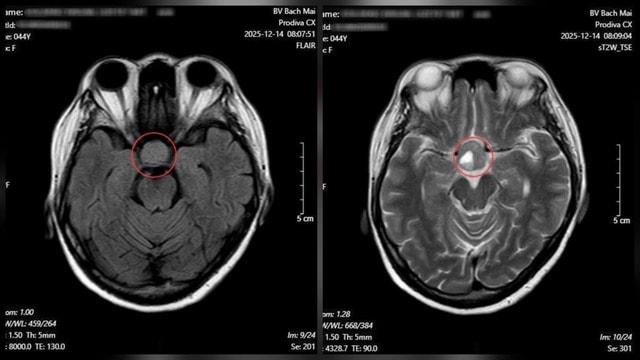

Từ những dấu hiệu nghi ngờ, bệnh nhân được chỉ định chụp cộng hưởng từ (MRI) sọ não. Kết quả cho thấy một khối u tuyến yên kích thước lớn (macroadenoma), đo được 26 × 21 mm. Ngay sau đó, người bệnh được chuyển sang chuyên khoa Phẫu thuật Thần kinh để tư vấn điều trị và lên kế hoạch phẫu thuật nhằm tránh các biến chứng nặng nề hơn.